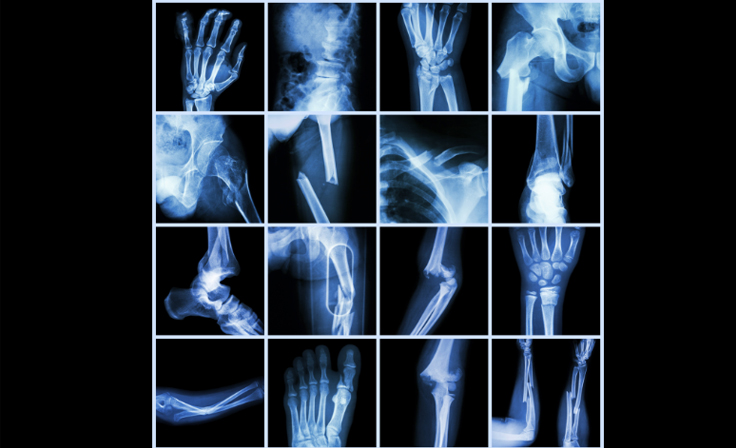

Fracture locations and their management approaches

Image